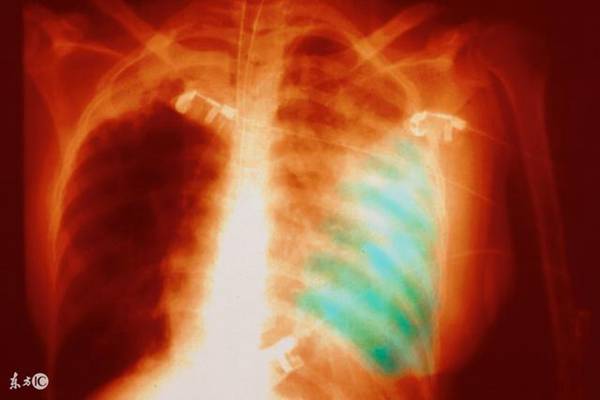

1、病变从上呼吸道开始,有充血、单核细胞浸润,向支气管和肺蔓延,呈间质性肺炎或斑片融合性支气管肺炎。一般起病缓渐,有乏力、咽痛、咳嗽、发热、纳差、肌痛等。半数病例无症状。X线显示肺部多种形态的浸润影,呈节段性分布,以肺下野为多见,有的从肺门附近向外伸展。支气体肺炎可在3-4周自行消散。儿童可并发鼓膜炎和中耳炎,伴有血液(急性溶血、血小板减少性紫癜)或神经(周围性神经炎、胸膜炎等)等并发症或雷诺现象(受冷时四肢间歇苍白或紫绀并感疼痛)时,则病程延长。